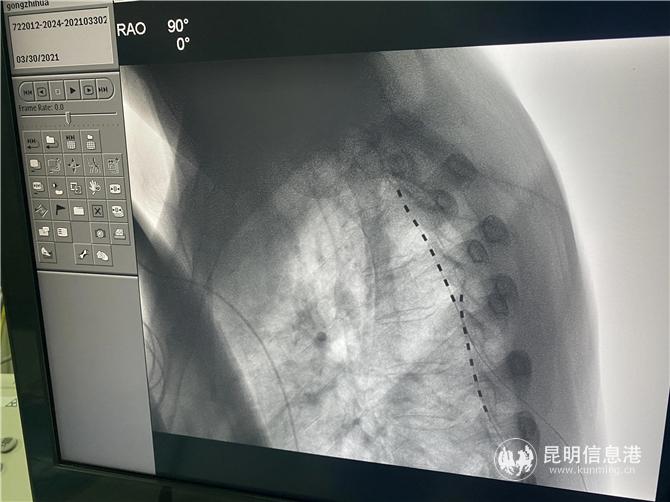

3月31日,在多学科团队的配合下,龚会军在介入杂交手术室、用局麻下为患者植入电极,由于患者之前的陈旧性损伤,患者的脊柱结构黏黏严重,给上行穿刺造成了极大的困难,同时,术中患者的疼痛位置又发生了变化,龚会军团队及时调整,术中测试患者疼痛区域全覆盖。术后,龚志华的疼痛明显缓解。(昆明信息港 记者孙红亮)